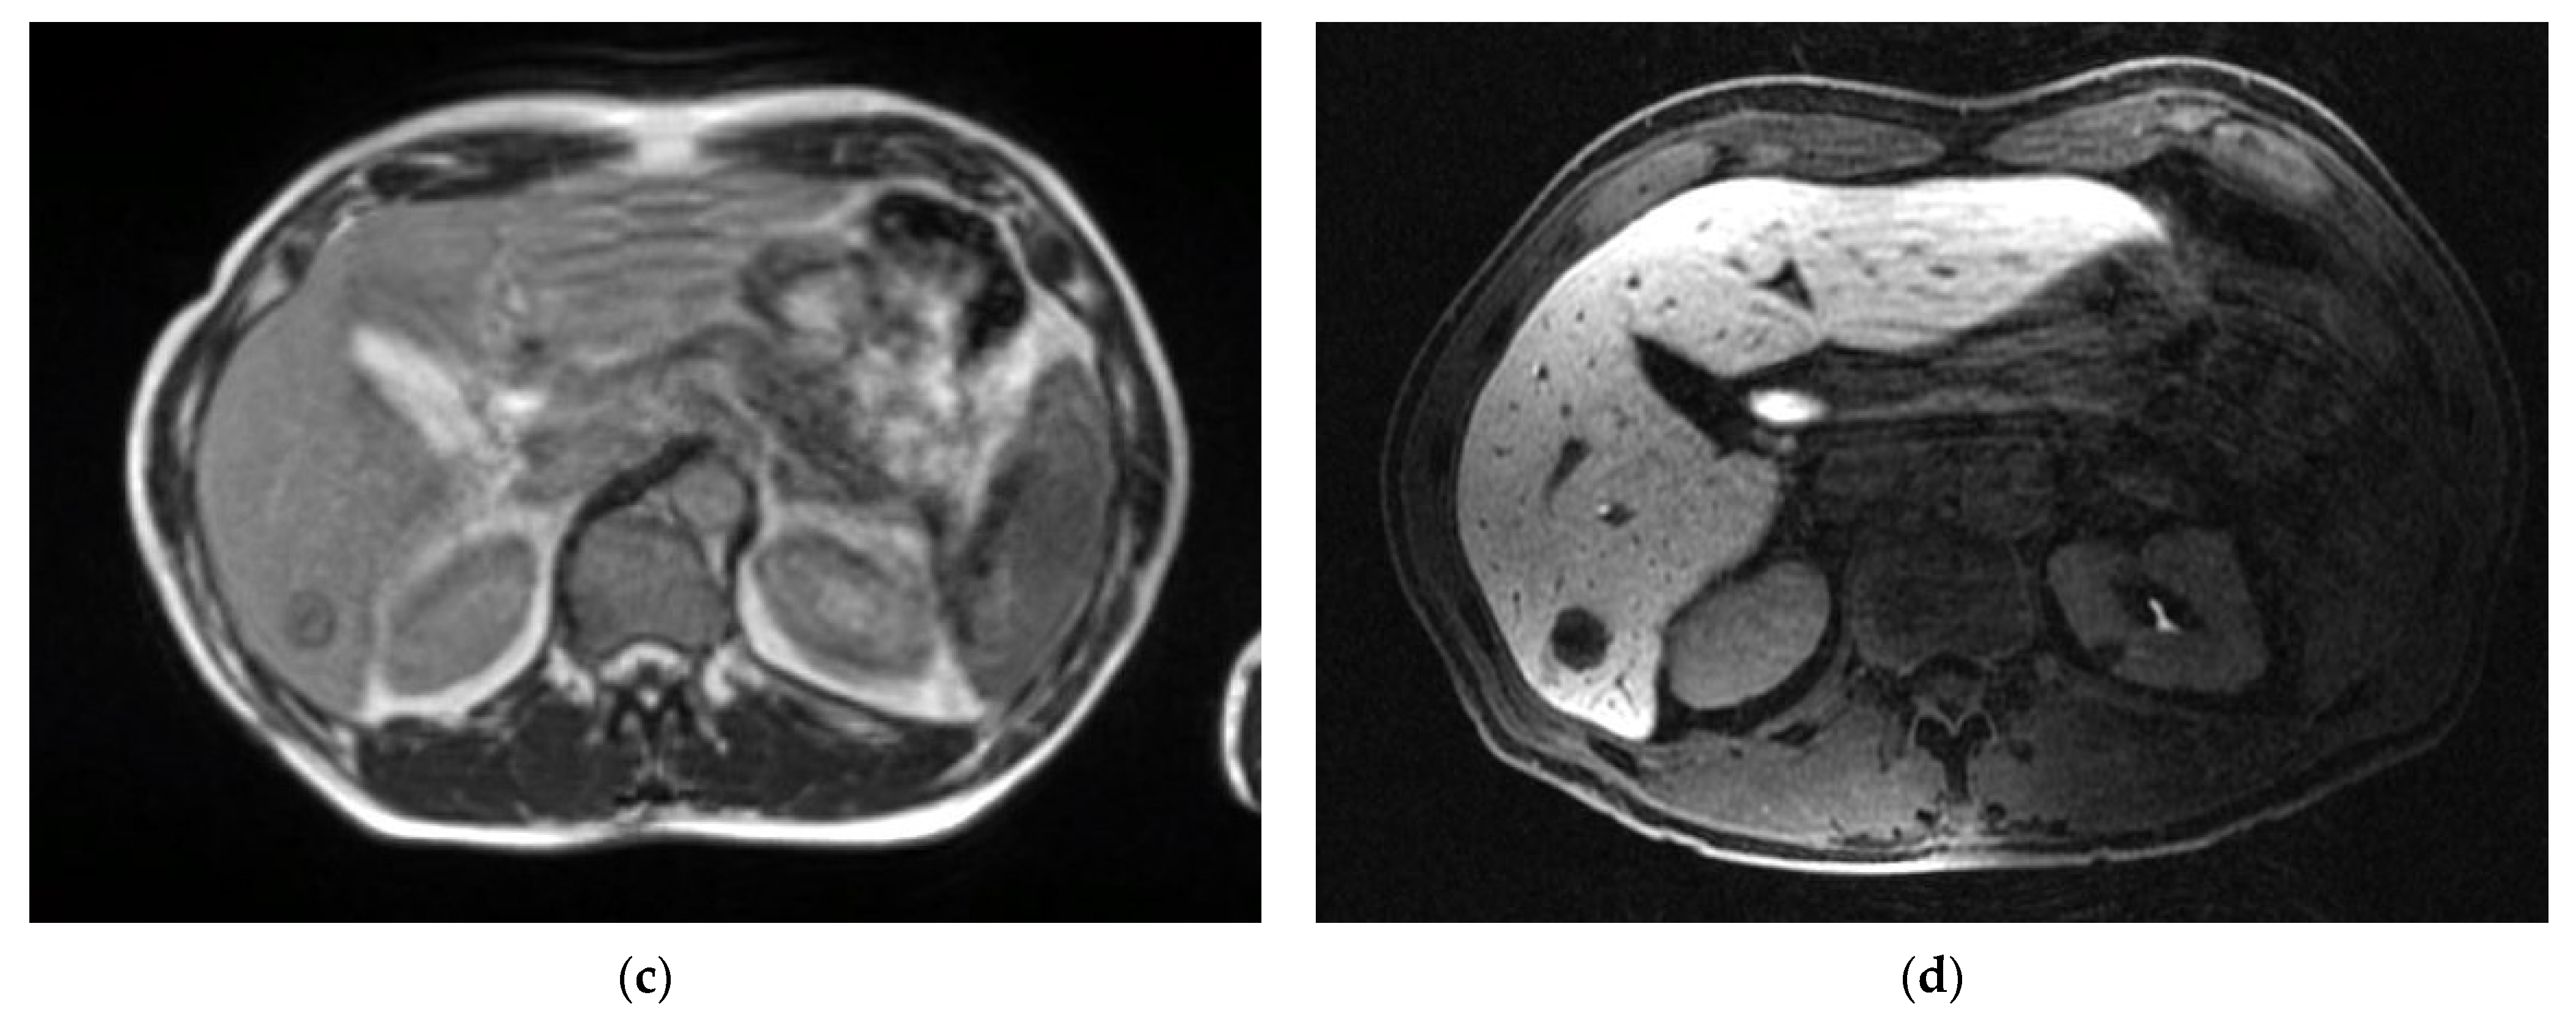

- Noel, C.E.; Parikh, P.J.; Spencer, C.R.; Green, O.L.; Hu, Y.; Mutic, S.; Olsen, J.R. Comparison of onboard low-field magnetic resonance imaging versus onboard computed tomography for anatomy visualization in radiotherapy. Acta Oncol. 2015, 54, 1474–1482. [Google Scholar] [CrossRef]

- Otazo, R.; Lambin, P.; Pignol, J.P.; Ladd, M.E.; Schlemmer, H.P.; Baumann, M.; Hricak, H. MRI-guided Radiation Therapy: An Emerging Paradigm in Adaptive Radiation Oncology. Radiology 2021, 298, 248–260. [Google Scholar] [CrossRef] [PubMed]